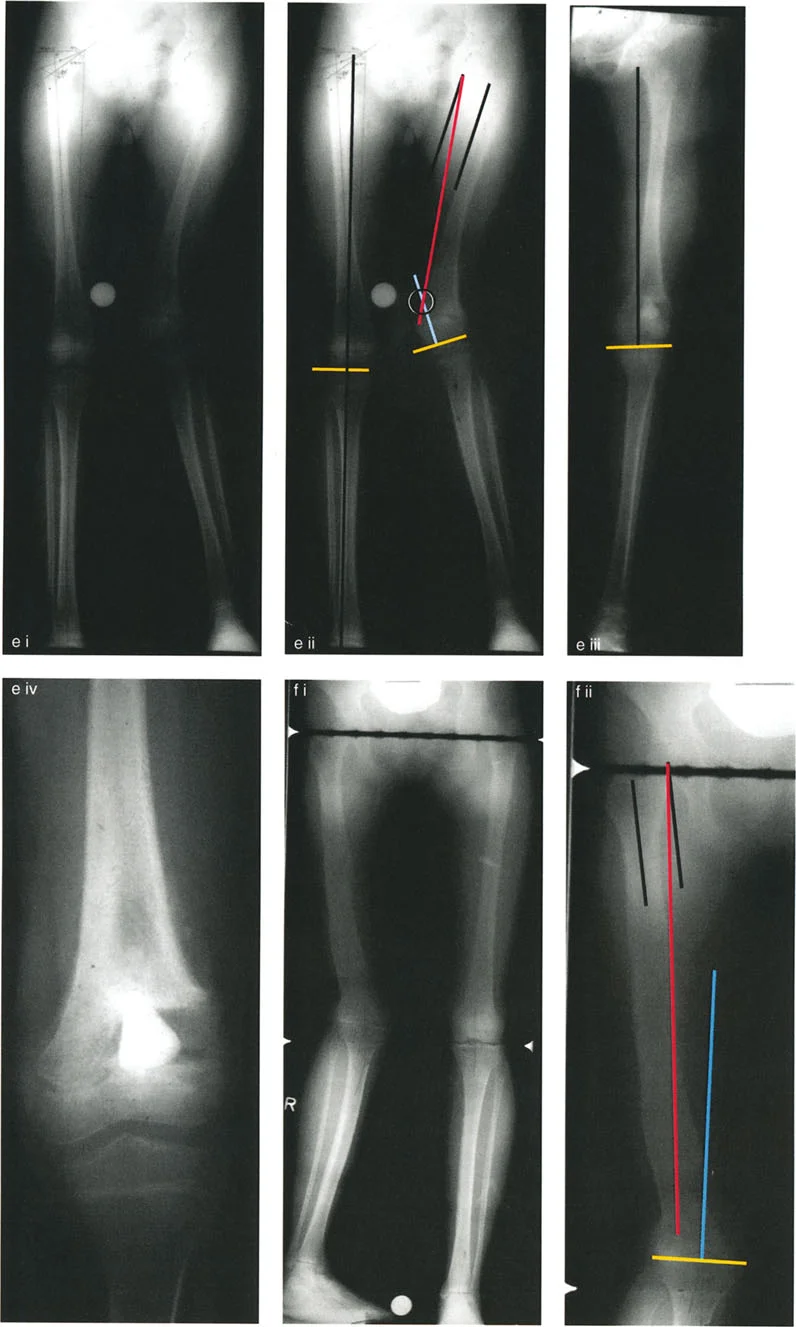

To determine exactly where the deformity lies (femur versus tibia, proximal versus distal), the surgeon must perform the Malorientation Test. This involves measuring specific joint orientation angles and comparing them to established normal population values.

Femoral Joint Orientation Angles

The femur is evaluated by drawing the mechanical axis of the femur (from the center of the femoral head to the center of the knee) and measuring its intersection with the joint lines.

- mLDFA (mechanical Lateral Distal Femoral Angle) This is the lateral angle formed between the mechanical axis of the femur and the distal femoral joint line. The normal value is 87 degrees, with a standard range of 85 to 90 degrees. An mLDFA greater than 90 degrees indicates a distal femoral varus deformity. An mLDFA less than 85 degrees indicates a distal femoral valgus deformity.

- MPTA (Mechanical Proximal Tibial Angle) This is the medial angle formed between the mechanical axis of the tibia and the proximal tibial joint line. The normal value is 87 degrees (range 85 to 90 degrees). An MPTA less than 85 degrees indicates proximal tibial varus. An MPTA greater than 90 degrees indicates proximal tibial valgus.

Center of Rotation of Angulation

The Center of Rotation of Angulation (CORA) represents the apex of the deformity. To find the CORA, the surgeon draws the Proximal Mechanical Axis (PMA) line and the Distal Mechanical Axis (DMA) line.

* The PMA is drawn by taking the normal joint orientation angle from the proximal joint and extending a line down the shaft.

* The DMA is drawn by taking the normal joint orientation angle from the distal joint and extending a line up the shaft.

* The exact point where the PMA and DMA intersect is the CORA.

A bone may have a single CORA (unapical deformity) or multiple CORAs (multi-apical deformity). Identifying the precise location of the CORA is the prerequisite for determining where to cut the bone and how to hinge the correction.

While the CORA is a fixed geometric point dictated by the patient's pathology, the Axis of Correction of Angulation (ACA) is the actual hinge point around which the bone segments are rotated during surgery.

The placement of the ACA is entirely under the surgeon's control. It can be placed on the convex cortex, the concave cortex, or even outside the bone entirely (as seen with external fixator hinges). The spatial relationship between the ACA and the CORA dictates the final alignment of the limb, the presence of translation, and changes in limb length.

Osteotomy Rule Two Angulation with Translation

The Geometric Definition

When the ACA passes through the CORA, but the osteotomy line is made at a different level (either proximal or distal to the CORA).

The Biomechanical Result

The mechanical axis and joint orientation angles are perfectly restored. However, because the bone cut is made at a distance from the hinge point, the bone segments will mathematically translate relative to one another. This creates a visible "bump" or step-off in the anatomic axis. While the bone looks jagged on an x-ray, the load-bearing mechanical axis is flawless.

Clinical Application

Rule Two is frequently used for juxta-articular deformities. For example, if a patient has a severe distal femoral valgus deformity, the CORA may be located inside the knee joint. A surgeon cannot perform an osteotomy through the articular cartilage. Therefore, the surgeon must place the ACA at the joint (the true CORA) but perform the actual bone cut (osteotomy) safely in the metaphysis.

The resulting translation is not an error; it is a necessary and mathematically sound compromise to achieve a straight mechanical axis while cutting the bone in a biologically safe zone.

Osteotomy Rule Three Secondary Deformity

The Geometric Definition

When the osteotomy line and the ACA are both placed at a level different from the CORA.

The Biomechanical Result

A secondary translational deformity is created. While the angular deformity may appear to be corrected, the mechanical axis will not be fully restored. The proximal and distal mechanical axes will be parallel but not collinear, resulting in residual Mechanical Axis Deviation (MAD).

Executing the Preoperative Plan

- Perform the Malalignment Test Draw the mechanical axis from the center of the femoral head to the center of the ankle. Measure the MAD. Determine if the mechanical axis falls in the medial, lateral, or central zone of the knee.

- Perform the Malorientation Test Draw the individual mechanical axes of the femur and tibia. Measure the mLDFA, MPTA, LPFA, and mLDTA. Compare these to normal values to isolate the source bone of the deformity.

- Locate the CORA Draw the Proximal Mechanical Axis (PMA) and Distal Mechanical Axis (DMA) using the normal joint orientation angles. Mark their intersection as the CORA.

- Select the Osteotomy Rule Determine if the bone can be safely cut at the CORA (Rule 1) or if the cut must be moved to the metaphysis (Rule 2).

Juxta Articular Deformities

Deformities located very close to the joint line present a unique challenge. The CORA is often located within the epiphysis or the joint space itself.

- Surgical Pearl You cannot cut through the CORA in these cases. You must utilize Paley's Rule 2. Place your hinge (ACA) at the joint line (the CORA), and perform your osteotomy in the metaphyseal bone.

- Managing Translation Be prepared for the resulting translation. When using a plate for fixation, you may need to use a specialized offset plate or manually contour the plate to accommodate the step-off. If using an intramedullary nail, blocking screws (Poller screws) are essential to guide the nail and maintain the translation without allowing the bone to slide back into deformity.

Multi Apical Deformities

Some bones, particularly those affected by metabolic bone disease (like Paget's or Osteogenesis Imperfecta) or complex trauma, will have multiple bends.

* Surgical Pearl A multi-apical deformity will have multiple CORAs. You must draw the PMA, an intermediate mechanical axis, and the DMA.

* Correction Strategy You can either perform multiple osteotomies (one at each CORA) or find a single "compromise CORA" that allows for a single cut. However, a single cut for a multi-apical deformity will almost always invoke Rule 3 and create significant translation, which may be cosmetically unacceptable or biomechanically unstable.